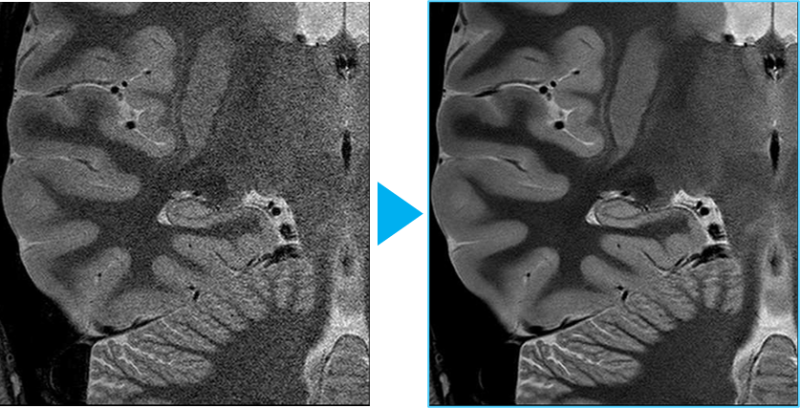

当院のMRI装置は、AI技術であるディープラーニングを設計段階で用いた先進技術を搭載しています。先進技術が搭載されたことにより、従来よりも短時間で高精細な検査を実現しています。加えて撮像時のMRI特有の大きな検査音を抑制する技術や広く明るい開放的な空間により、患者さんに快適な検査環境を提供しています。